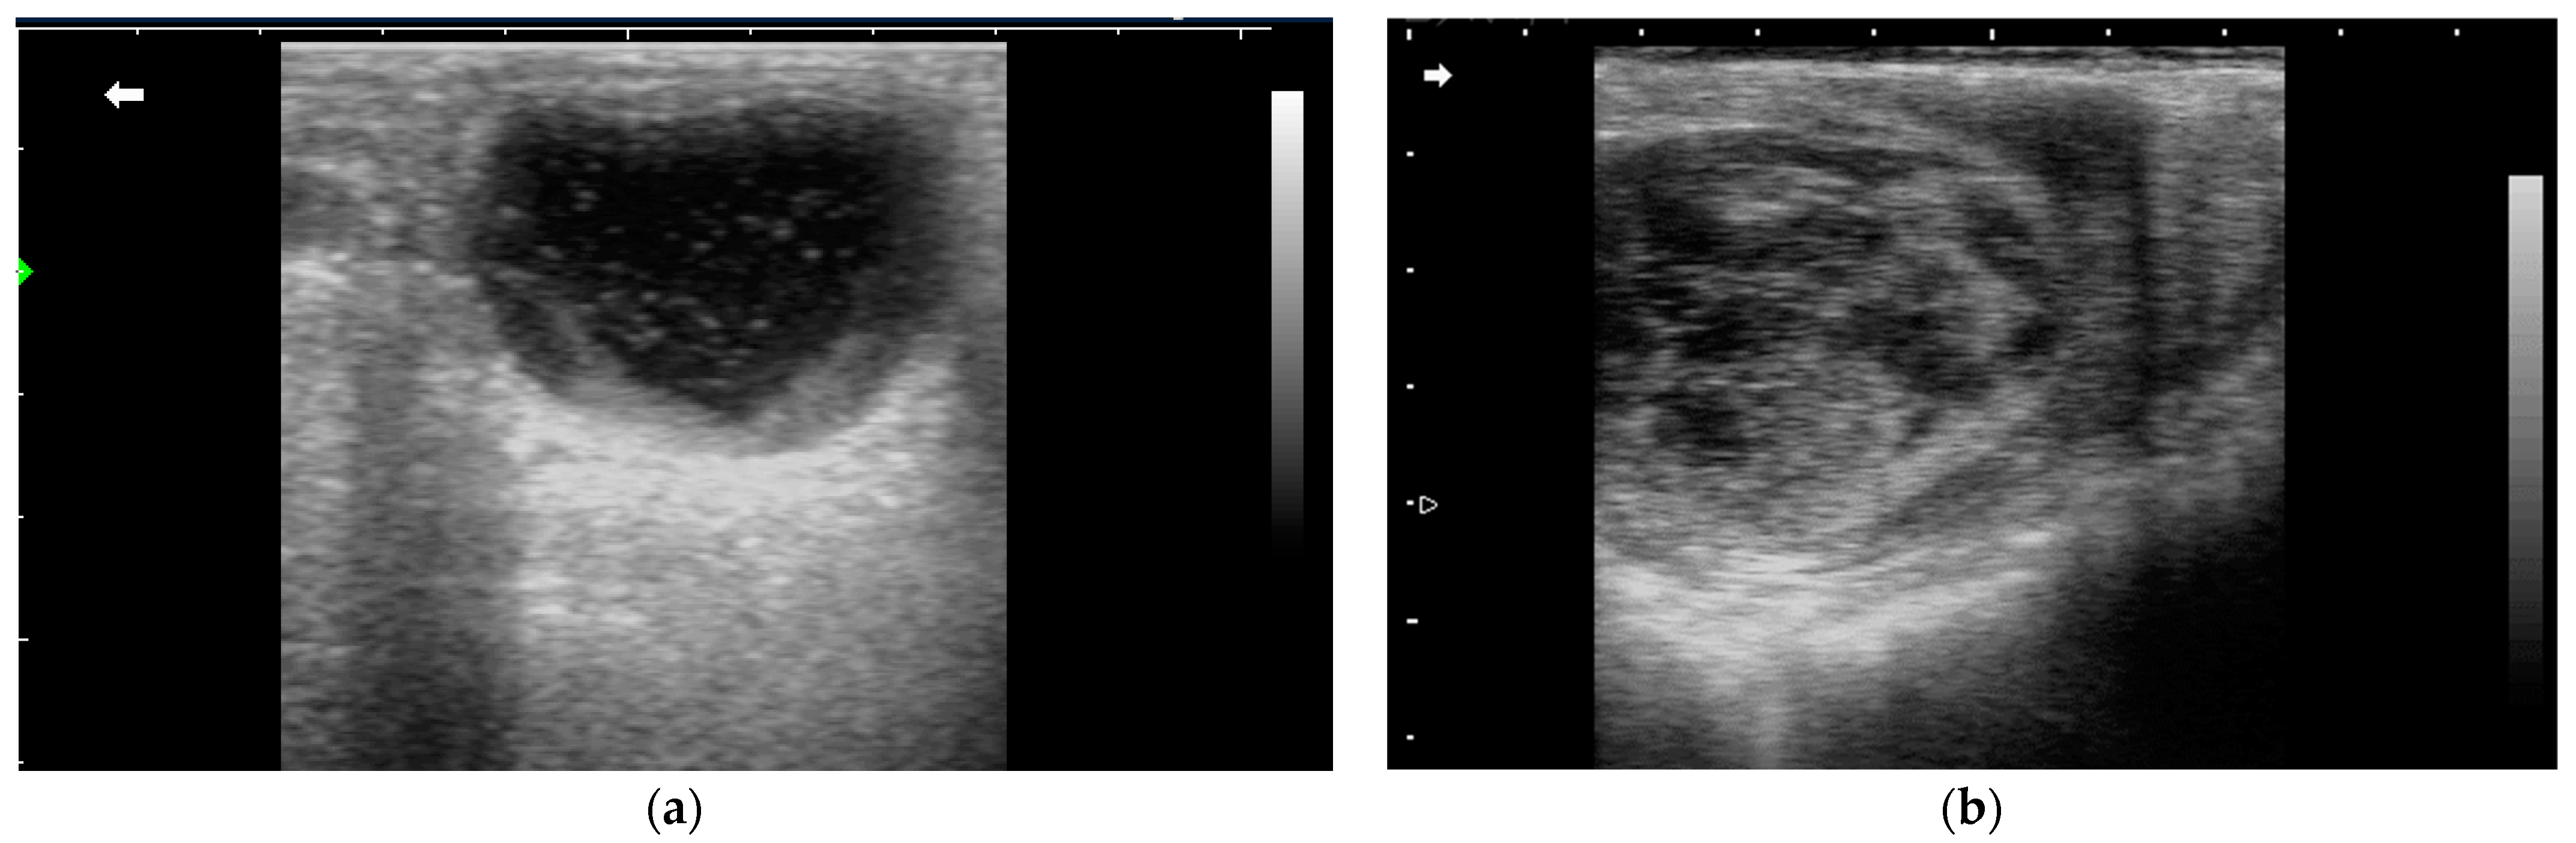

3.2.1. Anovulatory Follicles

- Ginther, O.; Gastal, E.; Gastal, M.; Beg, M.A. Incidence, endocrinology, vascularity, and morphology of hemorrhagic anovulatory follicles in mares. J. Equine Vet. Sci. 2007, 27, 130–139. [Google Scholar] [CrossRef]

- Segabinazzi, L.G.; Gilbert, R.O.; Ambrosia, R.L.; Bergfelt, D.R.; Samper, J.C.; Peterson, E.W.; French, H.M. Structural and Functional Dynamics of the Ovary and Uterus during the Estrous Cycle in Donkeys in the Eastern Caribbean. Animals 2022, 13, 74. [Google Scholar] [CrossRef] [PubMed]

- Hughes, E.; Ambrosia, R.; Gilbert, R.; French, H. Hemorrhagic anovulatory follicle in a tropical jenny. Clin. Theriogenol. 2018, 10, 119–123. [Google Scholar]

- Taberner, E.; Medrano, A.; Peña, A.; Rigau, T.; Miró, J. Oestrus cycle characteristics and prediction of ovulation in Catalonian jennies. Theriogenology 2008, 70, 1489–1497. [Google Scholar] [CrossRef]

| Donkey Breed | Location | Cycle Number | HAF Number (%) | Outcome | Reference |

|---|---|---|---|---|---|

| Dezhou Black donkey | China | 1083 | 49 (4.6%) | Unspecified | [59] |

| Caribbean donkey | West Indies | 31 | 1 (3.2%) | Ovulation in 19 days (contralateral ovary) | [61,62] |

| Catalonian donkey | Spain | 14 | 2 (14.3%) in the same jenny | Ovulation in 23 and 46 days, respectively | [63] |